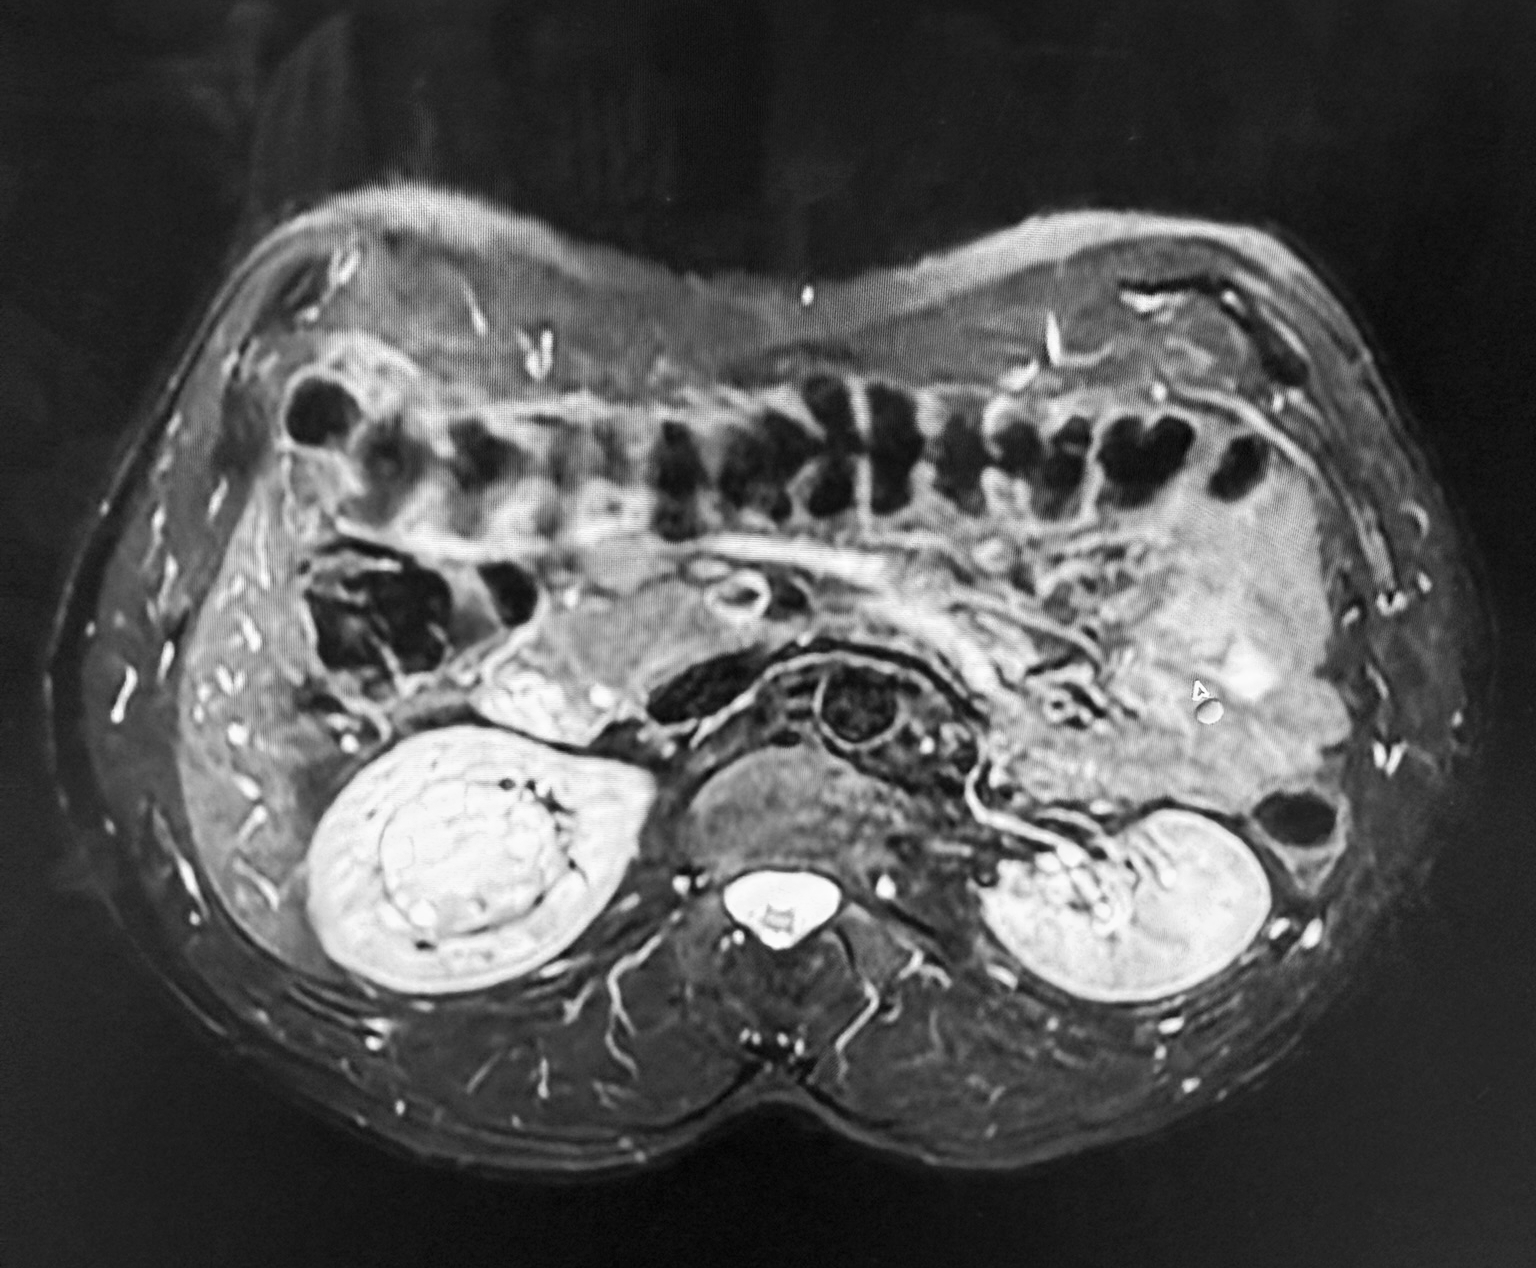

Zespół Klinicznego Oddziału Urologii i Onkologii Urologicznej Uniwersyteckiego Szpitala Klinicznego Nr 4 w Lublinie przeprowadził operację, którą lekarze określają jako jedną z najbardziej wymagających. U pacjenta wykryto guz nerki wielkości piłki tenisowej, zlokalizowany w samym centrum narządu – w bezpośrednim sąsiedztwie naczyń nerkowych. Mimo bardzo wysokiego ryzyka udało się go usunąć bez konieczności amputacji nerki.

Jak podkreślają specjaliści, większość guzów nerek rozwija się na obrzeżach narządu, co znacząco ułatwia ich usunięcie. W tym przypadku sytuacja była znacznie trudniejsza. Zmiana miała charakter endofityczny, czyli rosła wewnątrz miąższu nerki.

– Zwykle operujemy guzy o wielkości dwóch-trzech centymetrów. Tutaj zmiana była znacznie większa i ukryta głęboko w narządzie, tuż przy naczyniach. Konieczne było nacięcie nerki, precyzyjne wypreparowanie guza i zamknięcie powstałego ubytku. To bardzo wymagająca technicznie procedura – wyjaśnia dr n. med. Przemysław Mitura, pełniący obowiązki lekarza kierującego oddziałem.